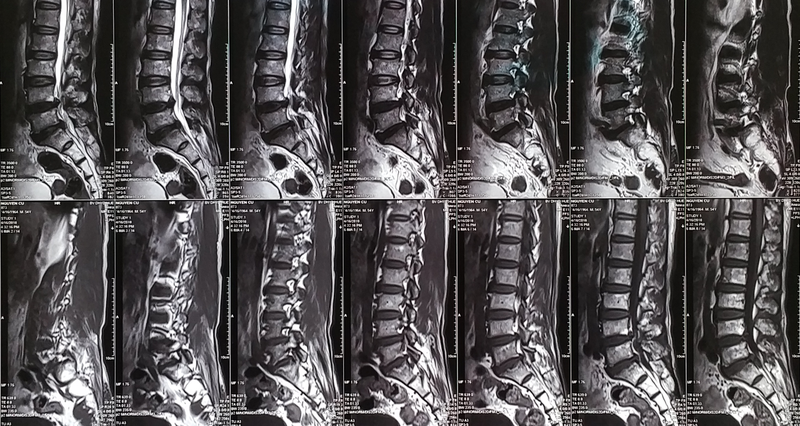

Dây thần kinh tọa bao gồm rất nhiều rễ thần kinh, bao gồm rễ L4, L5, S1, S2 và S3, tất cả đều thuộc một cấu trúc được gọi là đám rối thần kinh thắt lưng. Cấu trúc này chạy từ vùng thắt lưng xuống đến các ngón chân và đóng vai trò quan trọng trong việc điều khiển và chi phối các hoạt động của chi dưới.

Đám rối thần kinh thắt lưng có vị trí ở hai bên dọc theo cột sống thắt lưng và phía trước mỏm ngang đốt sống. Nó chạy phía trước cơ vuông thắt lưng, mang theo nhiệm vụ chi phối những vận động của cả hai chân và giúp thực hiện các động tác như gập, duỗi đầu gối, ngồi dậy, gập duỗi bàn chân và điều phối vận động của cả hai chân.

Để đưa ra chẩn đoán về tổn thương đám rối thần kinh thắt lưng, các phương pháp cận lâm sàng quan trọng bao gồm: